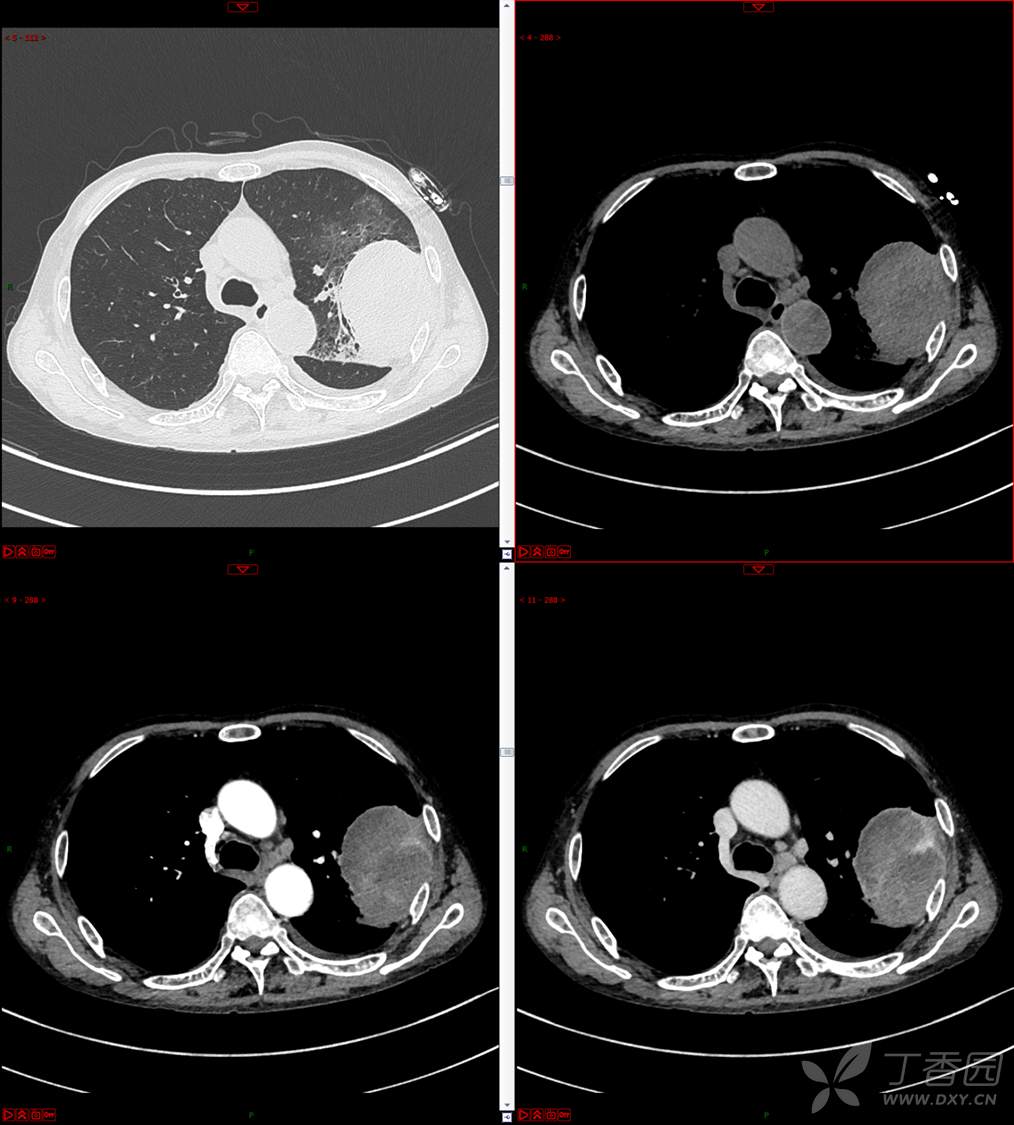

现病史:患者自诉5月前无明显原因及诱因出现纳差、乏力,伴进食后腹胀,无腹痛、腹泻、发热、盗汗、恶心、胸闷,未行特殊处理。1月前无明显原因诱因出现咳嗽,呈阵发性,咳白痰,痰中带鲜红色血丝,10余口/日,无血块,仍伴纳差、乏力、进食后腹胀,无恶心、呕吐、呕血,无头晕、心慌、喘憋、胸闷。在家未行特殊治疗,来我院就诊,2022.8.18行胸部(肺)CT平扫:左上肺占位并左侧肋骨骨质破坏,考虑间叶源性恶性肿瘤。门诊以“肺肿物”收入我科。患者自发病以来,神志清,精神可,饮食差,睡眠可,二便正常,近3月减轻5Kg。